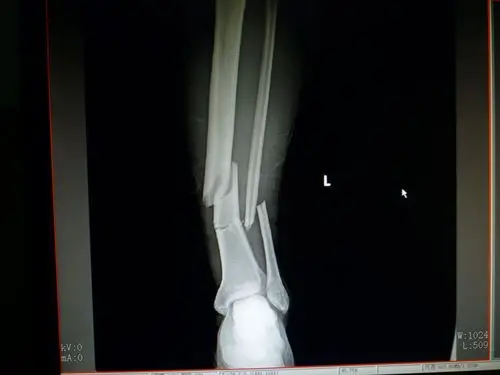

胫骨结节撕脱骨折

三例胫腓骨远端骨折

胫腓骨骨折